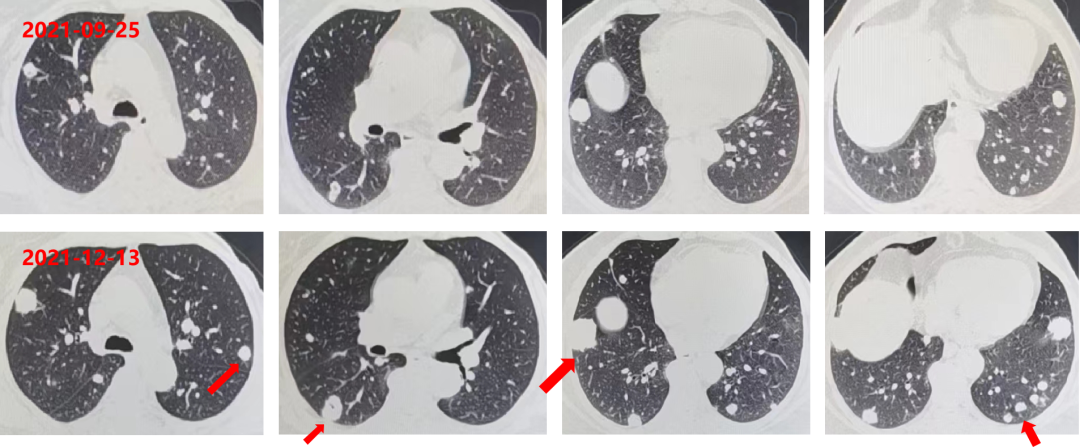

胸部增强CT:双肺多发转移瘤,部分较前片增大;直肠壁增厚,较前稍减小;肝左叶低密度影,较前片变化不大。

肺内靶病灶稳定,出现新病灶,疗效评估PD。

2021-12-13 复查 CEA:165.9ng/ml。

胸部+全腹部增强CT:直肠壁增厚,较前未变化;肝左叶低密度影,较前片未变化;双肺多发转移瘤(靶病灶及非靶病灶增大)。

疗效评估PD。